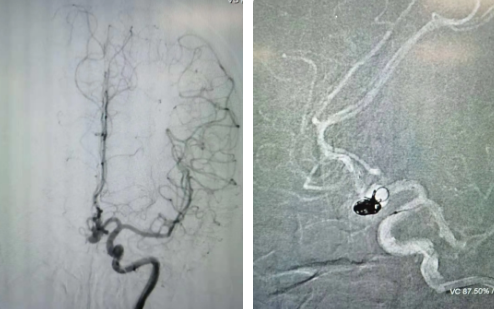

經(jīng)過全面仔細(xì)評估,西安國際醫(yī)學(xué)中心醫(yī)院神經(jīng)外科陸丹醫(yī)生決定采用微創(chuàng)介入進(jìn)行治療。在取得患者及家屬同意后,3月11日,陸丹醫(yī)生為患者行Atlas支架輔助顱內(nèi)動(dòng)脈瘤栓塞術(shù)。

腦血管較外周血管更為脆弱、迂曲,對術(shù)者的操作技術(shù)及精準(zhǔn)性要求特別高。術(shù)中,陸丹醫(yī)生通過股動(dòng)脈穿刺、置入微導(dǎo)管,再通過微導(dǎo)管將彈簧圏送入動(dòng)脈瘤腔內(nèi),利用彈簧圈的機(jī)械閉塞作用,達(dá)到防止動(dòng)脈瘤破裂的目的。術(shù)后,患者各項(xiàng)生命體征平穩(wěn)。

陸丹醫(yī)生介紹,此次腦科醫(yī)院首次采用Atlas支架輔助進(jìn)行顱內(nèi)動(dòng)脈瘤栓塞術(shù)。以往動(dòng)脈瘤栓塞術(shù)中的支架輸送導(dǎo)管較粗,支架順應(yīng)性差,易使載瘤動(dòng)脈移位,而Atlas支架的輸送導(dǎo)管很細(xì),輸送順滑,同時(shí)順應(yīng)性及貼壁性強(qiáng),能夠適應(yīng)迂曲的腦遠(yuǎn)端血管。